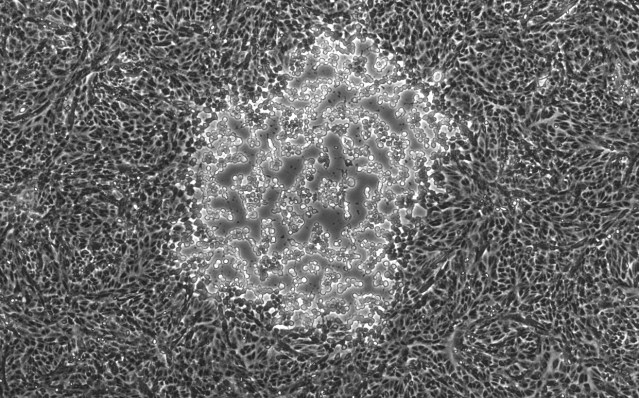

This image shows a focal point of infection by the herpes simplex virus type 1 (HSV-1) from one of the strains sequenced in research led by Moriah L. Szpara at Penn State University. Credit: Penn State University